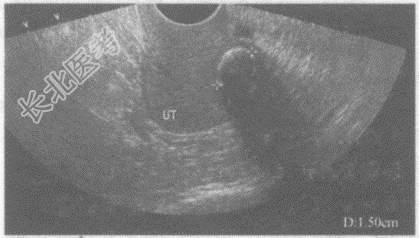

- 单项选择题临床资料:女性, 51岁,绝经2年, 常规体检。

超声综合描述:经阴道扫查子宫水平位, 测值减小,子宫内膜显示不清, 后壁可见低回声,内见直径1.5cm弧形强回声光带, 后伴声影。

其超声提示: A、子宫腺肌瘤

B、畸胎瘤

C、子宫肌瘤并钙化

D、子宫内膜息肉

E、子宫腔内异物